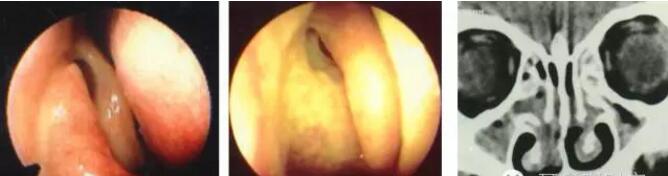

中鼻甲解剖变异:泡状中鼻甲

泡状中鼻甲感染及引起上颌窦口阻塞

中鼻甲解剖变异:中鼻甲反向弯曲

中鼻甲解剖变异与鼻窦炎